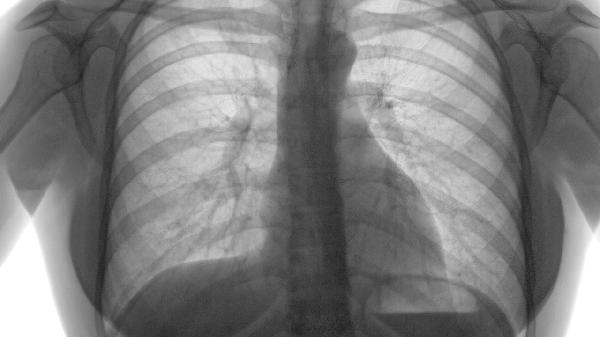

肺气肿片通常适用于慢性阻塞性肺疾病和支气管哮喘患者,主要成分为中药提取物,具有止咳化痰、平喘消肿的功效。